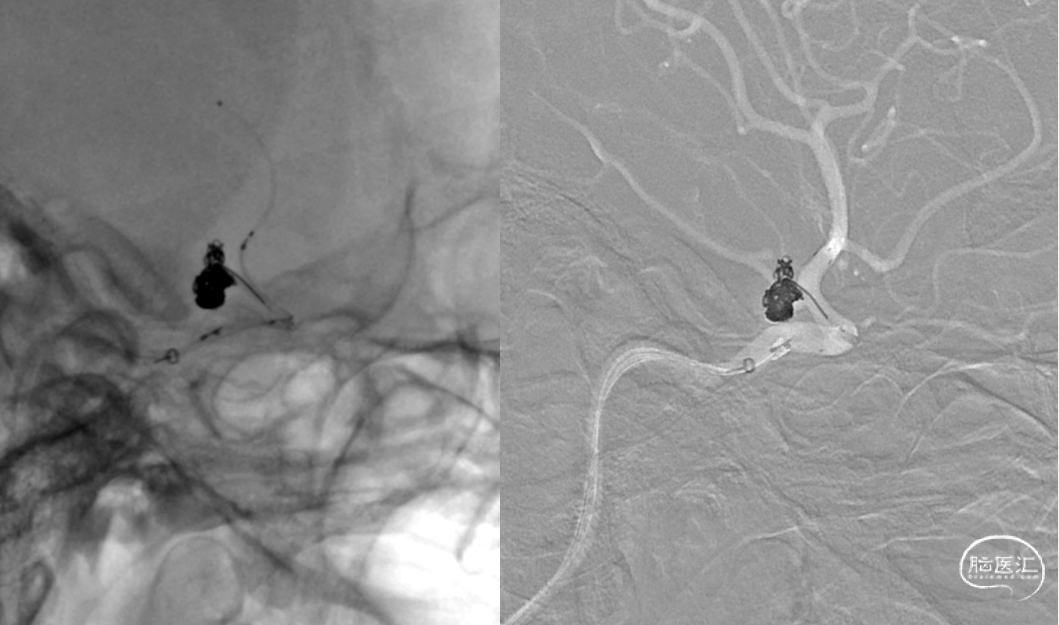

复查造影动脉瘤少量充盈,继续将3枚1mm*3cm弹簧圈(EV3)沿子瘤的Echelon-10微导管送入。复查造影示左侧颈内动脉、左大脑中动脉、大脑前动脉、左侧后交通动脉显影良好,动脉瘤栓塞完全。